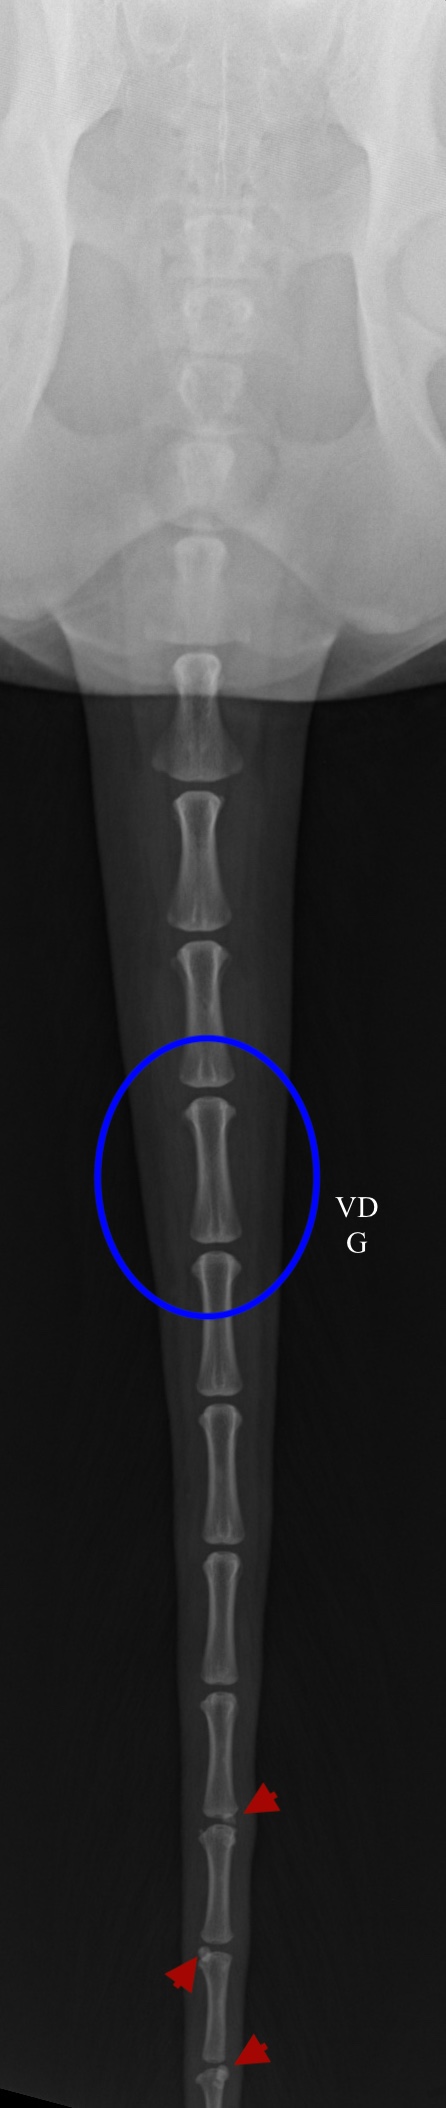

Des radiographies en vue dorso-ventrale et de profil droit de la queue sont réalisées Elles montrent l’intégrité de tous les espaces intervertébraux avec un alignement correct de la queue. Une discrète prolifération osseuse entre les vertèbres caudales Cd14-15, Cd15-16 et Cd16-17 est visualisée, pouvant être compatible avec des changements dégénératifs (ostéophytes). Aucune anomalie des structures extra- osseuses n’est visible sur ces clichés radiographiques. La jonction lombosacrée ne présente pas d’anomalie radiographique. Ces images radiographiques ne sont pas en mesure d’expliquer les symptômes.